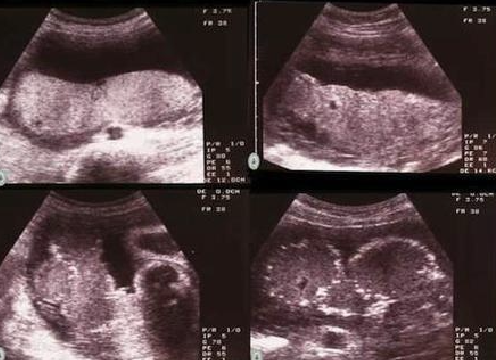

¿Cómo se evalúa el volumen de LA?

Índice de Phelan (suma 4 cuadrantes): Valor Normal: 8-16 cm. 📏

¿Qué valor de ILA indica oligoamnios?

<8 cm. ⚠️ VN: 8 a 16cm ## Footnote * Oligoamnios representa sin duda mayor riesgo para el feto * ILA menor de 8 indica Oligoamnios

10. ¿Qué valor de ILA indica oligoamnios? A. >16 cm B. 8-16 cm C. <8 cm D. >5 cm

C. <8 cm ILA: Índice de Líquido Amniótico. ⚠️